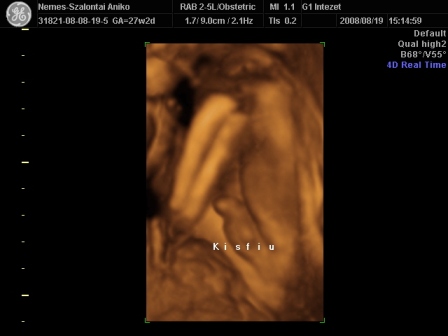

Én Óbudán a G1 intézetben voltam 4D-n. Régen ők voltak a Schöpf-Méreiben. Nagyon-nagyon kedvesek voltak. Nem kaptam letolást, mert késtünk sajnos a dugó miatt. Mondták telefonban, hogy ne idegeskedjek, csak menjünk :D .

Egy nagyon kedves hölgy vizsgált. Mindent megtett, hogy a lehető legjobb képet tudja csinálni a piciről. Nem volt könnyű dolga, mert végig háttal volt, a pofikája előtt volt a köldökzsinór, a két keze és az egyik talpa :lol: . Tornász lesz a gyerek :D . Viszont a fiússágát rögtön megmutatta. Összesen fél órás volt a vizsgálat. A picur méretei teljesen megfelelnek annak, ahány hetes vagyok. Eszerint nov. 9. és 16. között születik. Nem tudom, hogy a saját dokim, honnan szedett 20-át? Mindegy, úgyis akkor jön, amikor jönnie kell. A súlya a picinek 1103 g :) . Jó a szívhang és a köldökzsinór véráramlása is.

Készült DVD az egész vizsgálatról. 4 fényképet kinyomtattak, amit mi választottunk ki. És feltöltötték a honlapjukra az összes képet, amit egy kapott kóddal megnézhet bárki 30 napig. Így a távoli-külföldi rokonok is rögtön láthatják a bébit :).

Szóval teljesen elégedett voltam. Nekem a vizsgálat (hála a babaszobának) ingyenes volt, amúgy 13e Ft.

Ez már tuti, hogy fiú

Kis pofikája I.

Kis pofikája II.

És a tornász pozíció